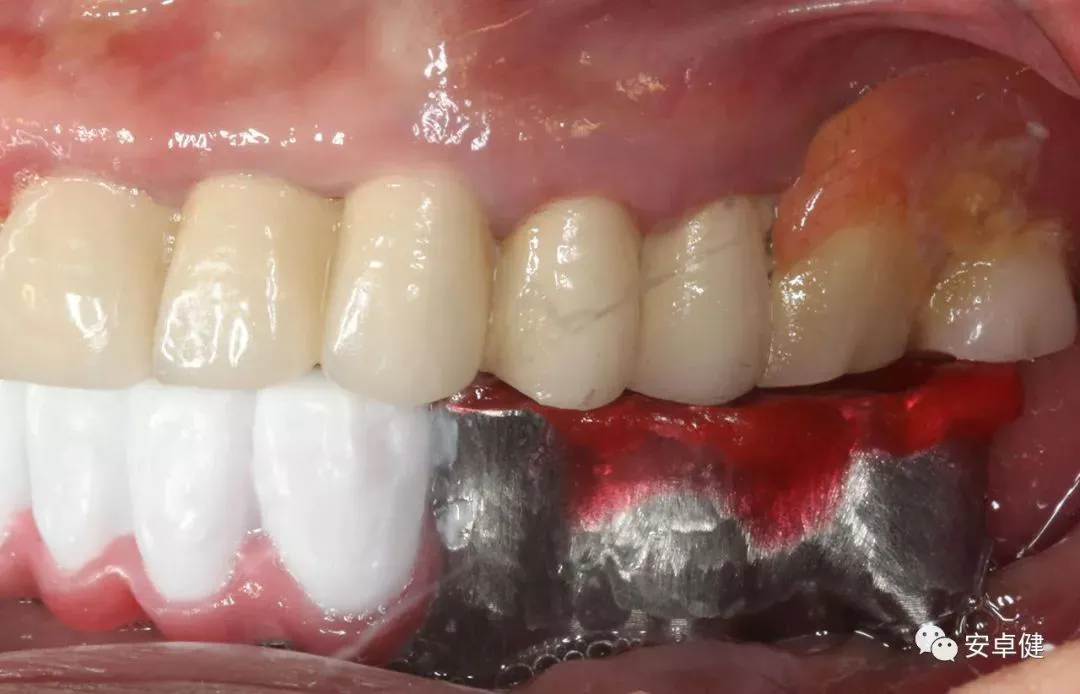

种植术后一年复诊侧面照a.

种植术后一年复诊侧面照b.